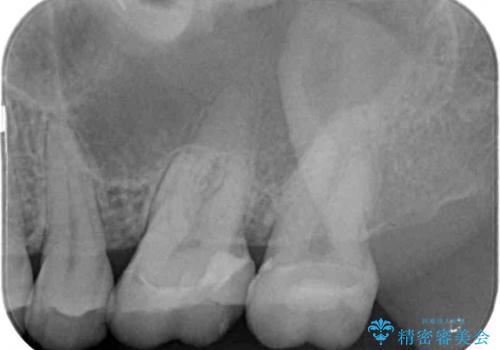

レントゲン写真から、神経組織近くにまで大きな修復物が認められました。

叩いたり、冷熱や電気刺激にによるテストを行ったりとしましたが、炎症の状態は芳しくなく、根管治療を行う前提で処置を行うこととしました。